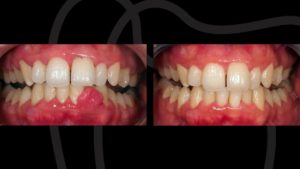

Cuando además de los síntomas de la gingivitis, se produce retracción de encías y/o perdida del hueso podemos afirmar que existe periodontitis. Si esta patología no la controlamos y la tratamos, el diente comenzará a moverse, apareciendo los famosos triángulos negros o huecos interdentales que tanto afectan a la estética. El paciente también puede sufrir molestias al masticar.

Los signos más comunes de la gingivitis son la inflamación de la encía, dolor leve, coloración rojo intenso y sangrado de encías.

Es la fase temprana de la enfermedad periodontal. Aparece cuando se acumula placa bacteriana o sarro que ataca a las encías. Afecta principalmente al hueso sin llegar a afectar al hueso.